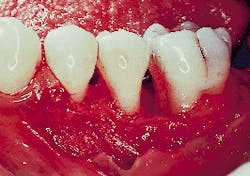

A large deposit of calculus can be seen on the mesial aspect of the molar in Figure 2. Recognizing that the bony defect had an excellent prognosis for bone fill, the root surface was debrided via hand instruments and ultrasonic scaling. The surrounding three walls of bone were then punctured (decorticated) so as to allow blood to exit the narrow spaces and enter the defect. As previously mentioned the blood forms a clot onto which new bone will develop.

Figure 2: A clinical view of the defect on the mesial aspect of tooth #19 subsequent to flap elevation, note the calculus deposit on the mesial root. The defect adjacent to the first molar is a three-wall defect.